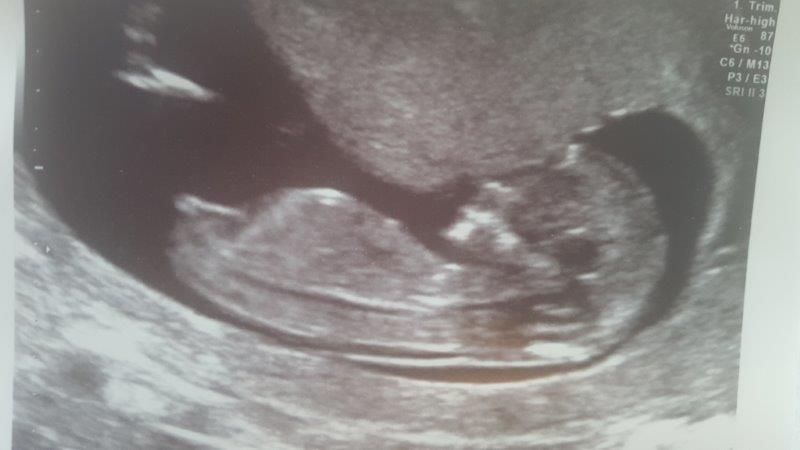

What do you think? I'm not going to officially ask at the next scan but would be interested to see your views. Won't believe anything until I see our little baby with my own eyes ;)

We have 2 gorgeous boys, this is baby no 3.

That's your girl!!

If that is not a girl I would be very surprised. At 13 weeks that is a lovely flat nub :))

Perfect girl nub!!!

Just clearing out my browser and found this website so thought I had better reply in case anyone else is interested. She was indeed a girl :)